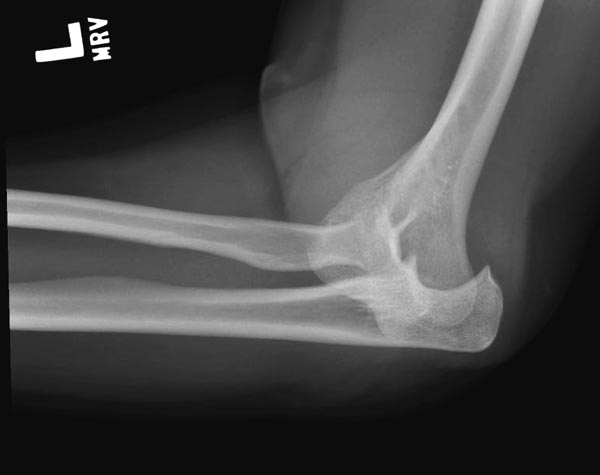

Один снимок всего? Может КТ-срезы какие-нибудь есть, R-снимки без гипса фас/профиль? По этому снимку вроде бы и нет вдавленного перелома. Суставная поверхность расколота - это да, но импрессии не увидел. Мы бы попытались сохранить головку.

На представленных снимках есть смещение суставной поверхности. Принцип лечения внутрисуставных переломов - восстановление суставной поверхности. У нас есть опыт восстановления таких переломов микровинтами. Удачи!

Вместе обычных простых рентгенограм, участились злоупотребления дорогими исследованиями. Хотя многие переломы, даже внутрисуставные, можно увидеть на обычных рентген снимках. Негативный рентген при исследовании локтевого сустава не означает отсутствие перелома. Если имеется “fat pad sign”, характерный симптом для внутрисуставных повреждений, тогда можно ставить диагноз перелом головки луча! Гематома внутрисуставного перелома смещает жировое тело и на боковом снимке проявляется в виде “паруса”.

Для выработки показаний достаточным бывают стандартные снимки, но иногда требуется косая рентгенограмма по Coyle. И для подтверждения смещений и оценки внутрисуставных фрагментов рекомендуется КТ, а 3D снимки показывают только поверхность, т.е. получается общая картина. МРТ дает возможность оценить состоянии связок.

Переломы по Mason первой степени без блокировки и смещение до 2х мм можно лечить в обычной косынке, или брейсом - консервативно. Перелом второй степени оперативно, а многооскольчатые переломы третьей степени лечатся заменой головки.